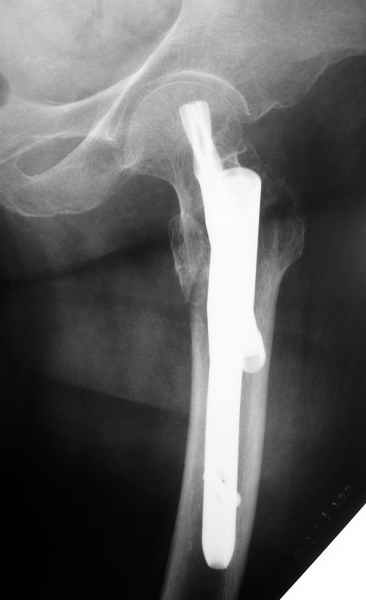

Как раз недавно у меня был примерный случай: больному 36 лет, поступил ночью, травма в результате мотоциклетной аварии, кроме чрезвертельного и спирального перелома левого бедра имеется переломы костей предплечья с этой же стороны. Скелетное вытяжение, а на следующий день больной про оперирован на ортопедическом столе с дистракцией. Чтобы не расколоть чрезвертельный перелом провели временную спицу ближе к переднему кортексу, из малого разреза костодержатель для репозиции, а фиксацию провели антиградным штифтом. Этапы операции на снимках.

Да, сейчас это и у нас самый напрашивающийся выбор. Сделали гвоздем ChM, картинки в приложении.